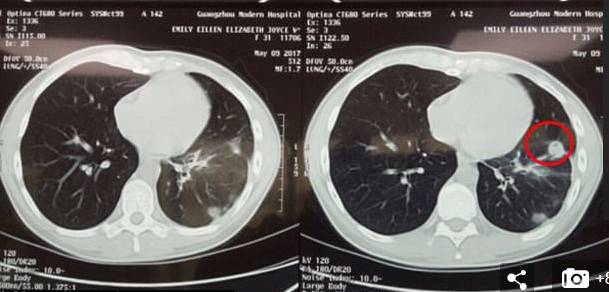

医院为Emily进行了一系列非常详细的检查,发现虽然已是癌症晚期,但是病人的精神没有垮!而且癌症发现的时间比较早,病人一直接受治疗,那么病人还是有希望的。

医院便安排了一系列对她的治疗:介入治疗、免疫治疗和冷冻治疗。

Emily当时就觉得身体舒服了好多了。她一日之内比一日之内觉得更好,而且她的肿瘤细胞数和血检水平都已恢复正常。

before/after

只用了四天时间,就有大约3cm的肿瘤排出体外,大概是肿瘤的一半大小。